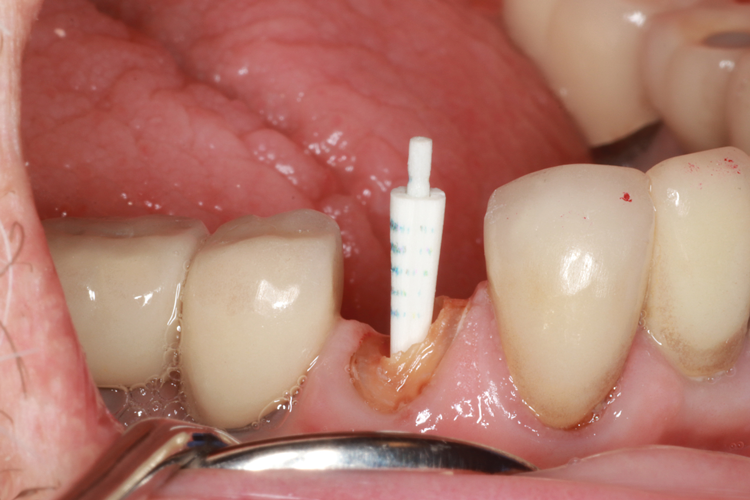

(5.) Prepared tooth with an oval shaped access before and after insertion of an oval-shaped post.

Figure 5